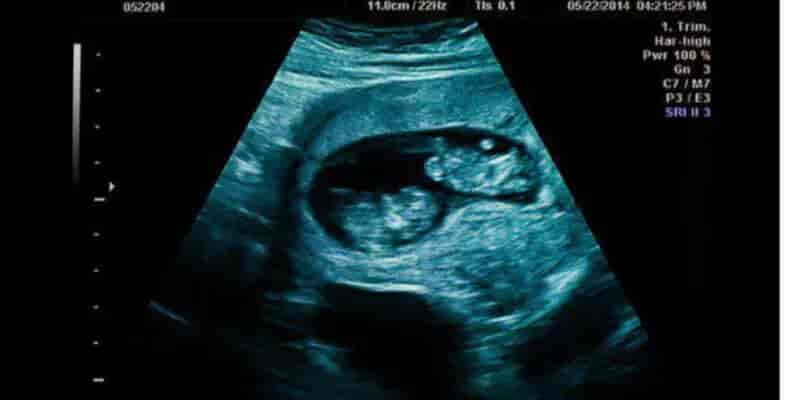

Είμαι έγκυος σε δίδυμα. Ο σύντροφός μου με εγκατέλειψε. Να κάνω έκτpωσn;

Μια γυναίκα μοιράζεται την ιστορία της εγκυμοσύνης της σε δίδυμα και τη συναισθηματική κατάρρευση που ακολούθησε, όταν ο σύντροφός της την εγκατέλειψε. Μέσα από το γράμμα της, αποτυπώνει τον διχασμό και την αγωνία της για το αν πρέπει να συνεχίσει ή να διακόψει την κύηση. Μια σχέση που προχώρησε γρήγορα Καλησπέρα. Το όνομά μου είναι […]Μετάβαση στην Πηγή